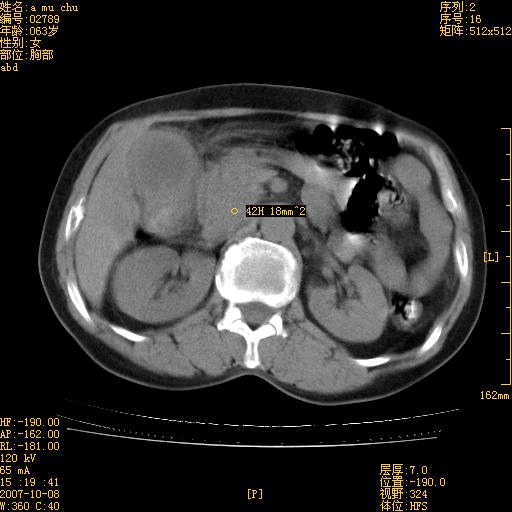

以下是引用王维浦在2007-10-17 21:02:00的发言:[br]胆囊增大,囊壁明显不规则增厚,邻近肝组织浸润,肝内外胆管无扩张。诊断:胆囊ca;[br]胰头软组织肿块影,考虑是由转移肿大的胰后淋巴结、没有肠道准备的十二指肠及胰头共同形成。[br]

以下是引用zhangzexing在2007-10-18 7:13:00的发言:[br]支持胰头占位,慢性胆囊炎. 2.肝左叶前外侧段占位,血管瘤?建议增强

以下是引用影像实习生在2007-10-17 19:49:00的发言:[br]支持胰头占位,慢性胆囊炎. 2.肝左叶前外侧段占位,血管瘤?建议增强.

以下是引用刘振江在2007-10-17 19:42:00的发言:[br]没有增强,胰头癌?胆囊及肝左叶占位?